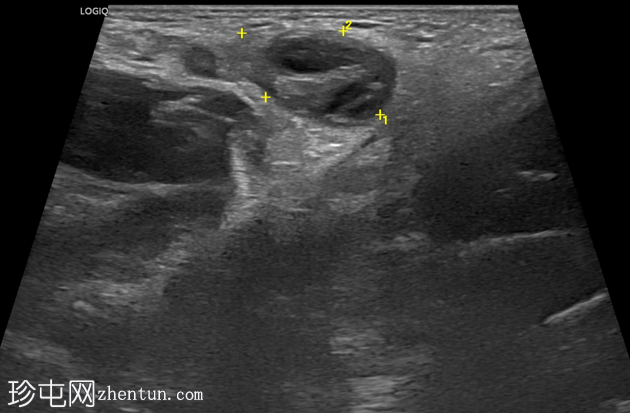

右侧努克氏疝管长约6毫米,内含部分子宫和卵巢(大小约1.5 x 1厘米)。在整个检查过程中,这些组织均保持原位。

对侧附件呈多囊性改变,大小约3 x 1.8厘米。

上述超声特征清晰地显示了努克氏疝管的内容物及其延伸范围;其中包含患者的一侧卵巢和部分子宫组织。

这些特征符合卵巢努克氏疝的诊断。